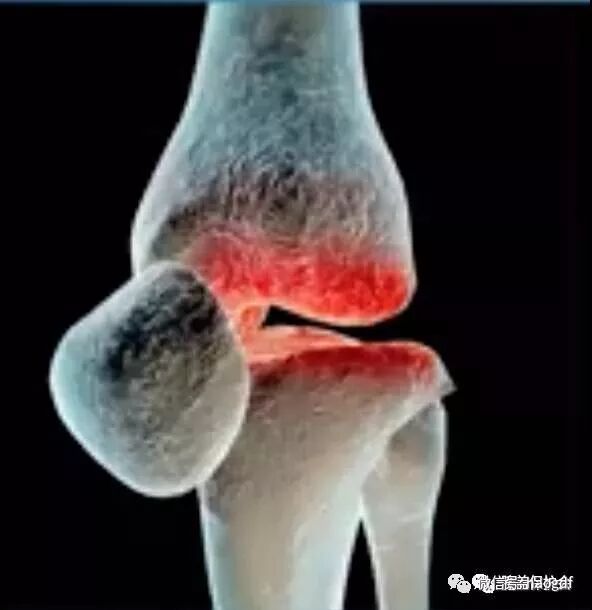

这个问题,其实就是膝盖退化所造成的。我们的膝盖在磨损的时候,内侧的半月板会磨损的比较快。

当内侧半月板变得比较窄外侧比较宽,也就是整个腿形向内凹下去的感觉,就变成O形腿了。

如果你在被动弯曲的时候,你连上图这样的90度都弯不下去的话,就很可能是因为你的关节面在弯曲超过90度这个角度的时候,它就开始摩擦关节面了。

因为你现在的关节面已经发炎的非常严重的地步,因为它一直被摩擦到磨损,你这样弯曲到九十度以下后,它就会让你痛到弯不下去,甚至让你觉得害怕到不敢弯曲不能弯曲了。